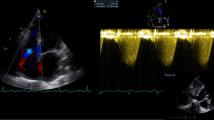

Echocardiography

All patients underwent a standard echocardiogram in keeping with current guidelines [11] employing a Vivid E9 ultrasound system (GE Ultrasound, Horten. Norway) equipped with a 2.5 MHz matrix array transducer. 2D gray-scale images were acquired at 50–80 frames/s over three heart cycles. Doppler tracings were recorded using a sweep speed of 100 mm/s. All images were subsequently exported and analyzed offline (EchoPAC PC, version 11.0.0.0 GE Ultrasound, Waukesha, Wisconsin) by experienced operators blinded to catheterization data. Left ventricular ejection fraction (LVEF) was estimated using the Simpson’s biplane method. PVRDoppler were calculated employing four different methods as previously described [5,6,7,8]. To estimate PVRDoppler in the two methods proposed by Abbas et al. [5, 6], peak tricuspid regurgitation velocity (TRVmax) was measured considering the most optimal signal obtained using apical and parasternal windows and right ventricular outflow tract velocity time index (RVOTVTI) was obtained by placing a 5 mm pulse-wave (PW) Doppler sample volume proximal to the pulmonary valve in the right ventricular outflow tract (RVOT) and tracing the resultant spectral wave form. For the method proposed by Scapellato et al. [7], pre-ejection period (PEP) was defined as time between QRS-start and RVOT-onset. Acceleration time (AcT) was expressed as the time between RVOT-onset and the RVOT-peak while total time (TT) was expressed as time interval between RVOT-onset and the RVOT-end. Finally, to estimate PVR using the method proposed by Haddad et al. RVOTVTI was measured as previously described, systolic pulmonary artery pressure (SPAP) was obtained by adding the recommended estimates of RA pressure [11] to the corresponding pressure gradient obtained from the TRVmax signal.